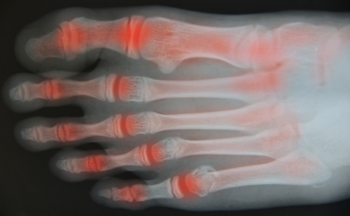

Managing Flare-Ups of Foot Arthritis

Foot arthritis is a condition where the joints in the foot become inflamed, leading to stiffness, swelling, and pain. It may result from wear and tear, autoimmune diseases, or injury. Flare-ups can be triggered by overexertion, stress, infection, or changes in activity, often causing increased joint pain and reduced mobility. These episodes may disrupt daily life and make walking or standing uncomfortable. A podiatrist can help manage symptoms through customized treatment plans, supportive footwear, orthotics, and lifestyle guidance. If you are experiencing ongoing joint pain in your feet, it is suggested that you consult a podiatrist who can provide effective relief and management techniques.

Arthritic Foot Care

Arthritis is a joint disorder that involves the inflammation of different joints in your body, such as those in your feet. Arthritis is often caused by a degenerative joint disease and causes mild to severe pain in all affected areas. In addition to this, swelling and stiffness in the affected joints can also be a common symptom of arthritis.

In many cases, wearing ill-fitting shoes can worsen the effects and pain of arthritis. Wearing shoes that have a lower heel and extra room can help your feet feel more comfortable. In cases of rheumatoid arthritis, the arch in your foot may become problematic. Buying shoes with proper arch support that contour to your feet can help immensely.

Alleviating Arthritic Pain

- Exercises that stretch the foot can prevent further pain and injury and increase mobility

- Most of the pain can be alleviated with anti-inflammatory drugs, heat, and topical medications

- Massages can help temporarily alleviate pain.

It is best to see your doctor for the treatment that is right for your needs and symptoms. Conditions vary, and a podiatrist can help you determine the right method of care for your feet.

Arthritic Foot Care

During your lifetime, you will probably walk about 75,000 miles, which is quite a lot of stress to put on your feet. As you get older, the 26 bones and 30 joints in each of your feet will lose flexibility and elasticity. Your foot’s natural shock absorbers will wear down as well. Having arthritis added to this mix only makes matters worse. Your joints will become distorted and inflamed, which is why arthritic foot care needs to be something to think about every day.

When dealing with arthritis, having additional foot complications, such as bunions, hammertoes, or neuroma, can be a serious detriment. To avoid these, buy well-fitting shoes with a lower heel and good support. Arthritis causes you to lose your arch, so having shoes with good arch support is also highly recommended.

Aside from getting good arch support, the shoes need to fit comfortably and properly as well. A good place to start is by leaving a finger width between the back of the shoe and your foot to gauge proper size. It is also helpful to have a square or rounded toe box in the front to provide even more comfort. Another thing to look for is a rubber sole that can provide a cushion and absorb shock as you walk. This adds flexibility to the ball of your foot when you push off your heel to walk.

Exercise is another key aspect of arthritic foot care. Exercise not only strengthens and stretches your muscles and joints, but helps to prevent further injury and pain as well. Stretching the Achilles tendon, the tendon located in the back of your heel, will give you added mobility and reduce pain due to stress. Another thing you can do is massage your feet, kneading the ball of your foot as well as your toes from top to bottom.

Stretching the Achilles tendon is a simple exercise that you can do at home anytime. Lean against the wall with your palms flat against the surface while placing one foot forward, towards the wall, and one foot behind you. Bend your forward knee towards the wall while keeping your back knee locked straight, and make sure both your heels are completely touching the ground at all times. This will stretch your Achilles tendon and calf muscles as well. You will feel the stretch almost immediately. You can also stretch your toes in a couple ways. One involves taking a rubber band and wrapping it around both your big toes while your heels remain together. Then, pull them apart to stretch your big toe. You can also place a rubber band around all the toes of one of your feet. Then, try to separate each individual toe, stretching them all.

A final step you can take to help your arthritis is taking non-steroid, non-inflammatory drugs or topical medicines with capsaicin. Unfortunately, there is no complete way to remove all of your arthritic pain. However, following some of this advice can go a long way in staying as pain-free as possible.